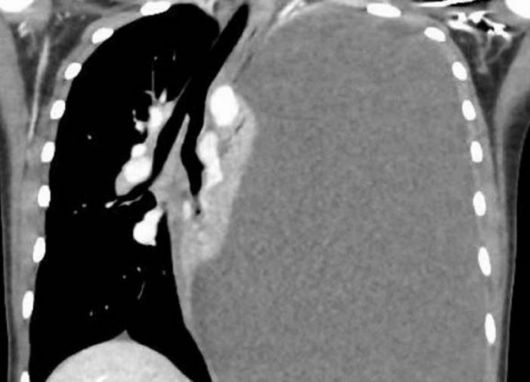

폐흡충 감염으로 대량 흉막 삼출액이 발생한 14세 여학생의 흉부 CT 사진. 의학사례보고저널 캡처 |

지난해 4월엔 14세 여학생이 호흡곤란과 함께 기침·피가 섞인 가래가 발생해 부산대 병원 응급실에 실려 왔다. 특별한 질환은 없었는데, 다만 가끔 가족과 민물 게를 먹었고 응급실에 오기 3개월 전 마지막으로 민물 게를 먹었다고 한다. 흉부 엑스레이 검사 결과 폐 흉막에 다량의 삼출액을 발견하고 삼출액을 즉시 빼냈다. 추가 검사 결과 기관지 폐포에서 폐흡충 알이 검출돼 폐흡충증 확진 판정을 받았다. 구충제를 경구 투여해 증상이 완화됐지만 여전히 폐가 쭈그러드는 ‘무기폐’ 상태가 지속돼 흉막 박피술을 진행했다.

폐흡충증은 우리나라에서 1960년대까지 비교적 흔한 질환이었지만 현재는 거의 보고되지 않는다. 민물 게를 이용한 음식 섭취에 의해 산발적으로 발생한다. 사람의 폐에 주로 자리를 잡고, 1.5~2.5cm 크기의 주머니를 형성해 그 안에 알을 낳는다. 마른 기침, 갑작스러운 호흡곤란, 복통 등의 증상이 나타나는데 구충제 프라지콴텔을 쓰면 대부분 제거된다.